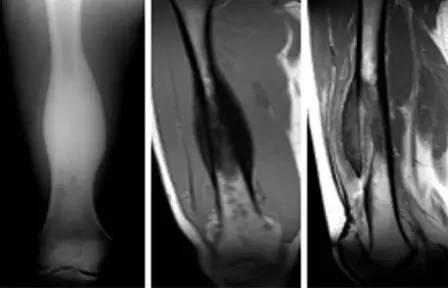

【病例】慢性骨髓炎1例X线及MR

女,23岁,右大腿反复肿痛3年。查体:右大腿粗大,压痛。

经诊断为慢性骨髓炎。

X线主要表现为广泛的增生、硬化,骨膜新生骨显著,甚至形成骨包壳,大片骨坏死脓腔和瘘道形成。骨内膜增生致髓腔变窄甚至闭塞消失,致使骨密度明显增高。骨外膜增厚、增浓,其深层与骨皮质融合,表面形成层状,导致骨干增粗,轮廓不规整。较大的死骨易于发现,小的死骨可为明显的骨硬化所掩盖。

CT比X线更容易发现死骨。慢性期,软组织肿胀仍存,时轻时重,甚至形成局限性软组织脓肿,边缘比较清楚。慢性化脓性骨髓炎趋向愈合时,脓腔及死骨消失。骨质增生硬化逐渐吸收,骨小梁逐渐清晰,骨髓腔又重新出现,骨皮质外形亦渐趋变平,厚度亦趋正常,但骨的畸形可持续存在一个较长时期。